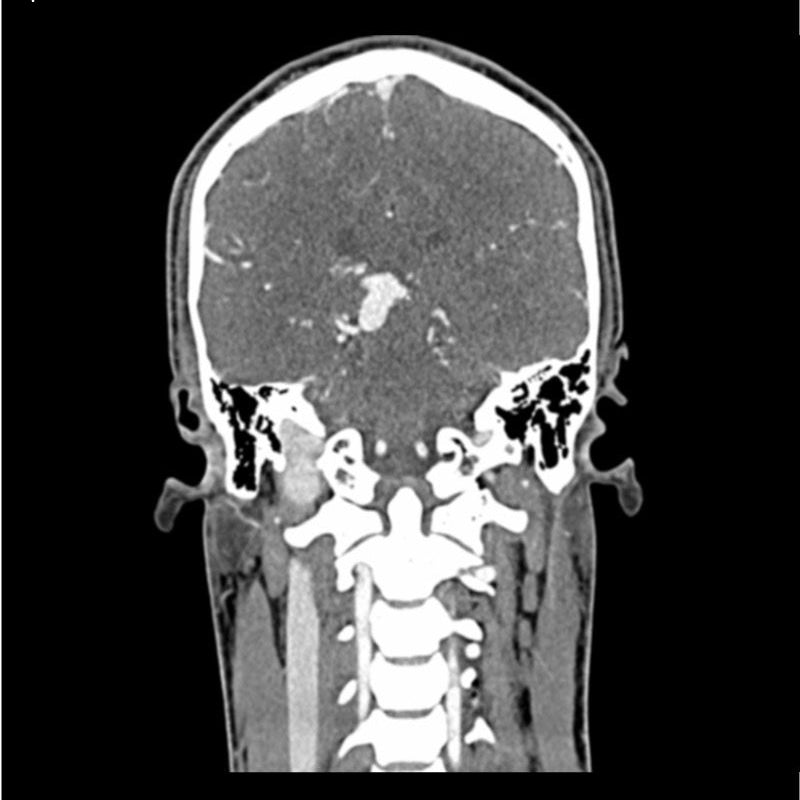

This phantom simulates a contrast medium enhanced head in arterial phase (CT angiography). It covers the vertex to the fifth cervical vertebra. The phantom has 10 low-contrast lesions in the centrum semiovale and the right hemisphere has an arteriovenous malformation.

The phantom can be used in CT (including CBCT) to evaluate and optimize imaging performance and AI-enabled diagnosis. It is also suited for training purposes. The phantom provides a detailed and realistic simulation of vascular structures, soft and bone tissue. Air voids are filled with a cellulose-polymer composite of approx. -160 HU.

Lesion diameter: 10 mm

Lesion height: 10.5 mm

Lesion contrast: Approx. -60 to -20 and 20 to 60 HU at 120 kVp